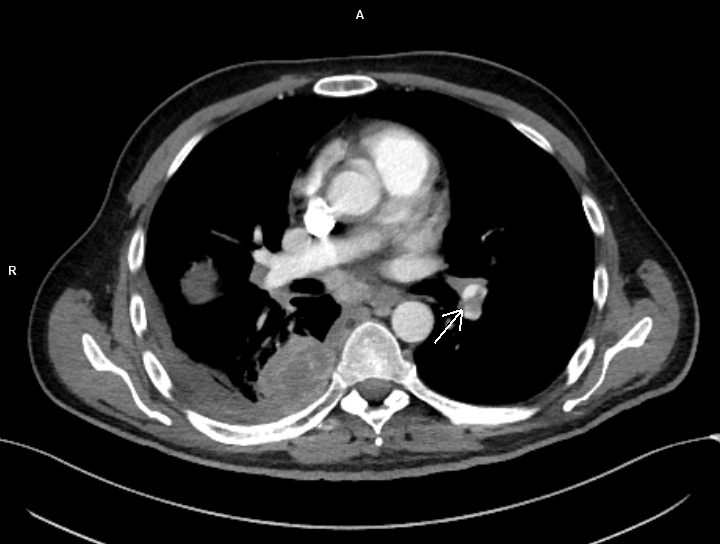

Figura 2: axial CT în timp arterial

Discuţie caz nr 99: pacientul s-a prezentat în urgență și a fost trimis la examinarea CT cu suspiciune de trombembolism pulmonar. Examinarea CT efectuată toracic care a surprins și o parte din abdomenul superior evidențiază trombembolism pulmonar acut stâng la nivelul arterei intermediare cu evoluție și la nivelul arterelor segmentare și subsegmentare precum și tumoră renală stânga de pol inferior cu aspect de carcinom cu celule clare (Grawitz) și determinări secundare pleurale drepte.